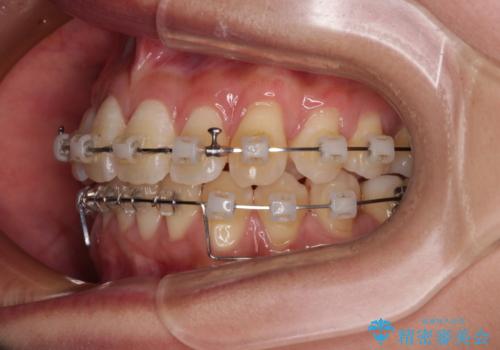

- クリアブラケット

- 1年6ヶ月

- 上顎前歯の突出感を気にして来院された患者様です。

舌の突出癖の影響で、歯列が前方に飛び出いた形態となっている状態でした。

抜歯矯正とするような歯列ではないため、舌のトレーニングを行いながら歯列を側方に拡大させることで口元の突出感を改善することとしました。